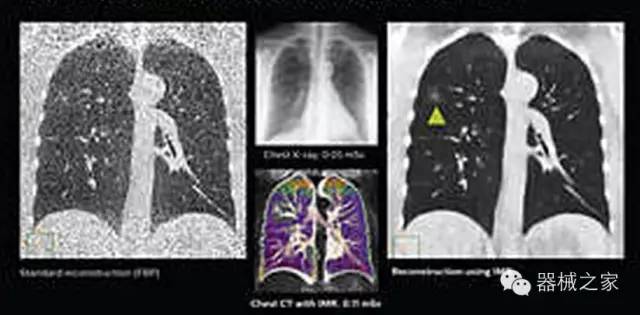

1.低劑量下的胸部顯影